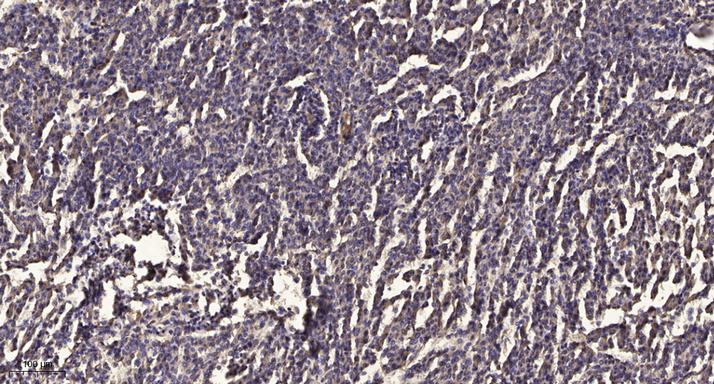

IHC (Immunohistochemistry)

(Immunohistochemical analysis of paraffin-embedded human meningioma. 1, Antibody was diluted at 1:200(4 degree overnight). 2, Tris-EDTA,pH9.0 was used for antigen retrieval. 3,Secondary antibody was diluted at 1:200(room temperature, 45min).)